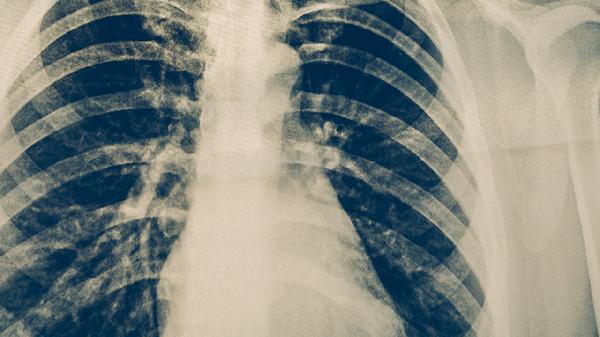

当症状持续不缓解或加重时需及时就医。医生会根据具体情况进行血常规、胸部X光等检查。明确诊断后可能需要进行抗病毒治疗、抗生素治疗或对症支持治疗。严重病例可能需要住院观察,接受静脉输液等综合治疗措施。